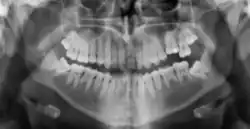

Radiographic appearance

On radiographs, enamel appears as the most radiopaque (white) structure due to its high mineral content.[19] Dentine and cementum are less radiopaque and are usually indistinguishable from each other.[19] The pulp chamber and root canals are radiolucent (dark), centrally located within the tooth structure. The periodontal ligament appears as a thin, radiolucent line between the root and the lamina dura.[19]